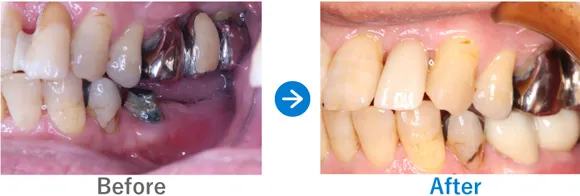

ほぼ虫歯な状態から、できるだけ歯を残した最小限のインプラントできれいな口元に

全顎ランパントカリエス(複数の歯に同時に虫歯が発生する状態)

インプラント4本:上顎2本、下顎2本、残せる歯はすべて補綴治療

4,917,000円(内訳:抜歯テルプラグ、GBR、根管治療、インプラント4本(ストローマン)、ガイド、全顎仮歯、補綴治療、セデーション、保証20年)

治療結果

まだお若いため、残せる歯はできるだけ残したうえで補綴治療(クラウンやブリッジなどによる治療)を行い、どうしても抜歯が必要な歯4本のみインプラントを行う方針で治療を進めました。

治療後は、見た目が整ったことはもちろん、しっかり噛めるようになったと喜んでいらっしゃいました。歯磨きが苦手とのことなので、定期メンテナンスでのアフターフォローも大切です。